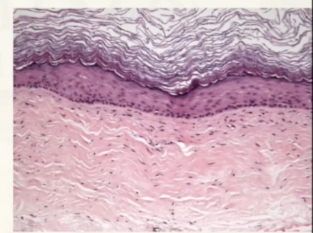

OKC’s have what kind of tissue

parakeratinized

orthokeratinized epithelium